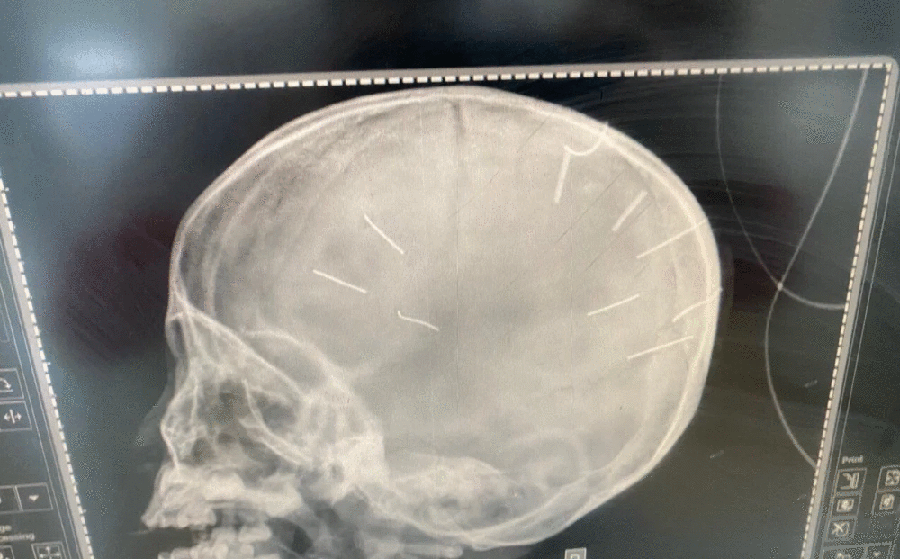

Hà Nội: Bé gái 3 tuổi nghi bị bạo hành, có nhiều vật thể lạ trong hộp sọ